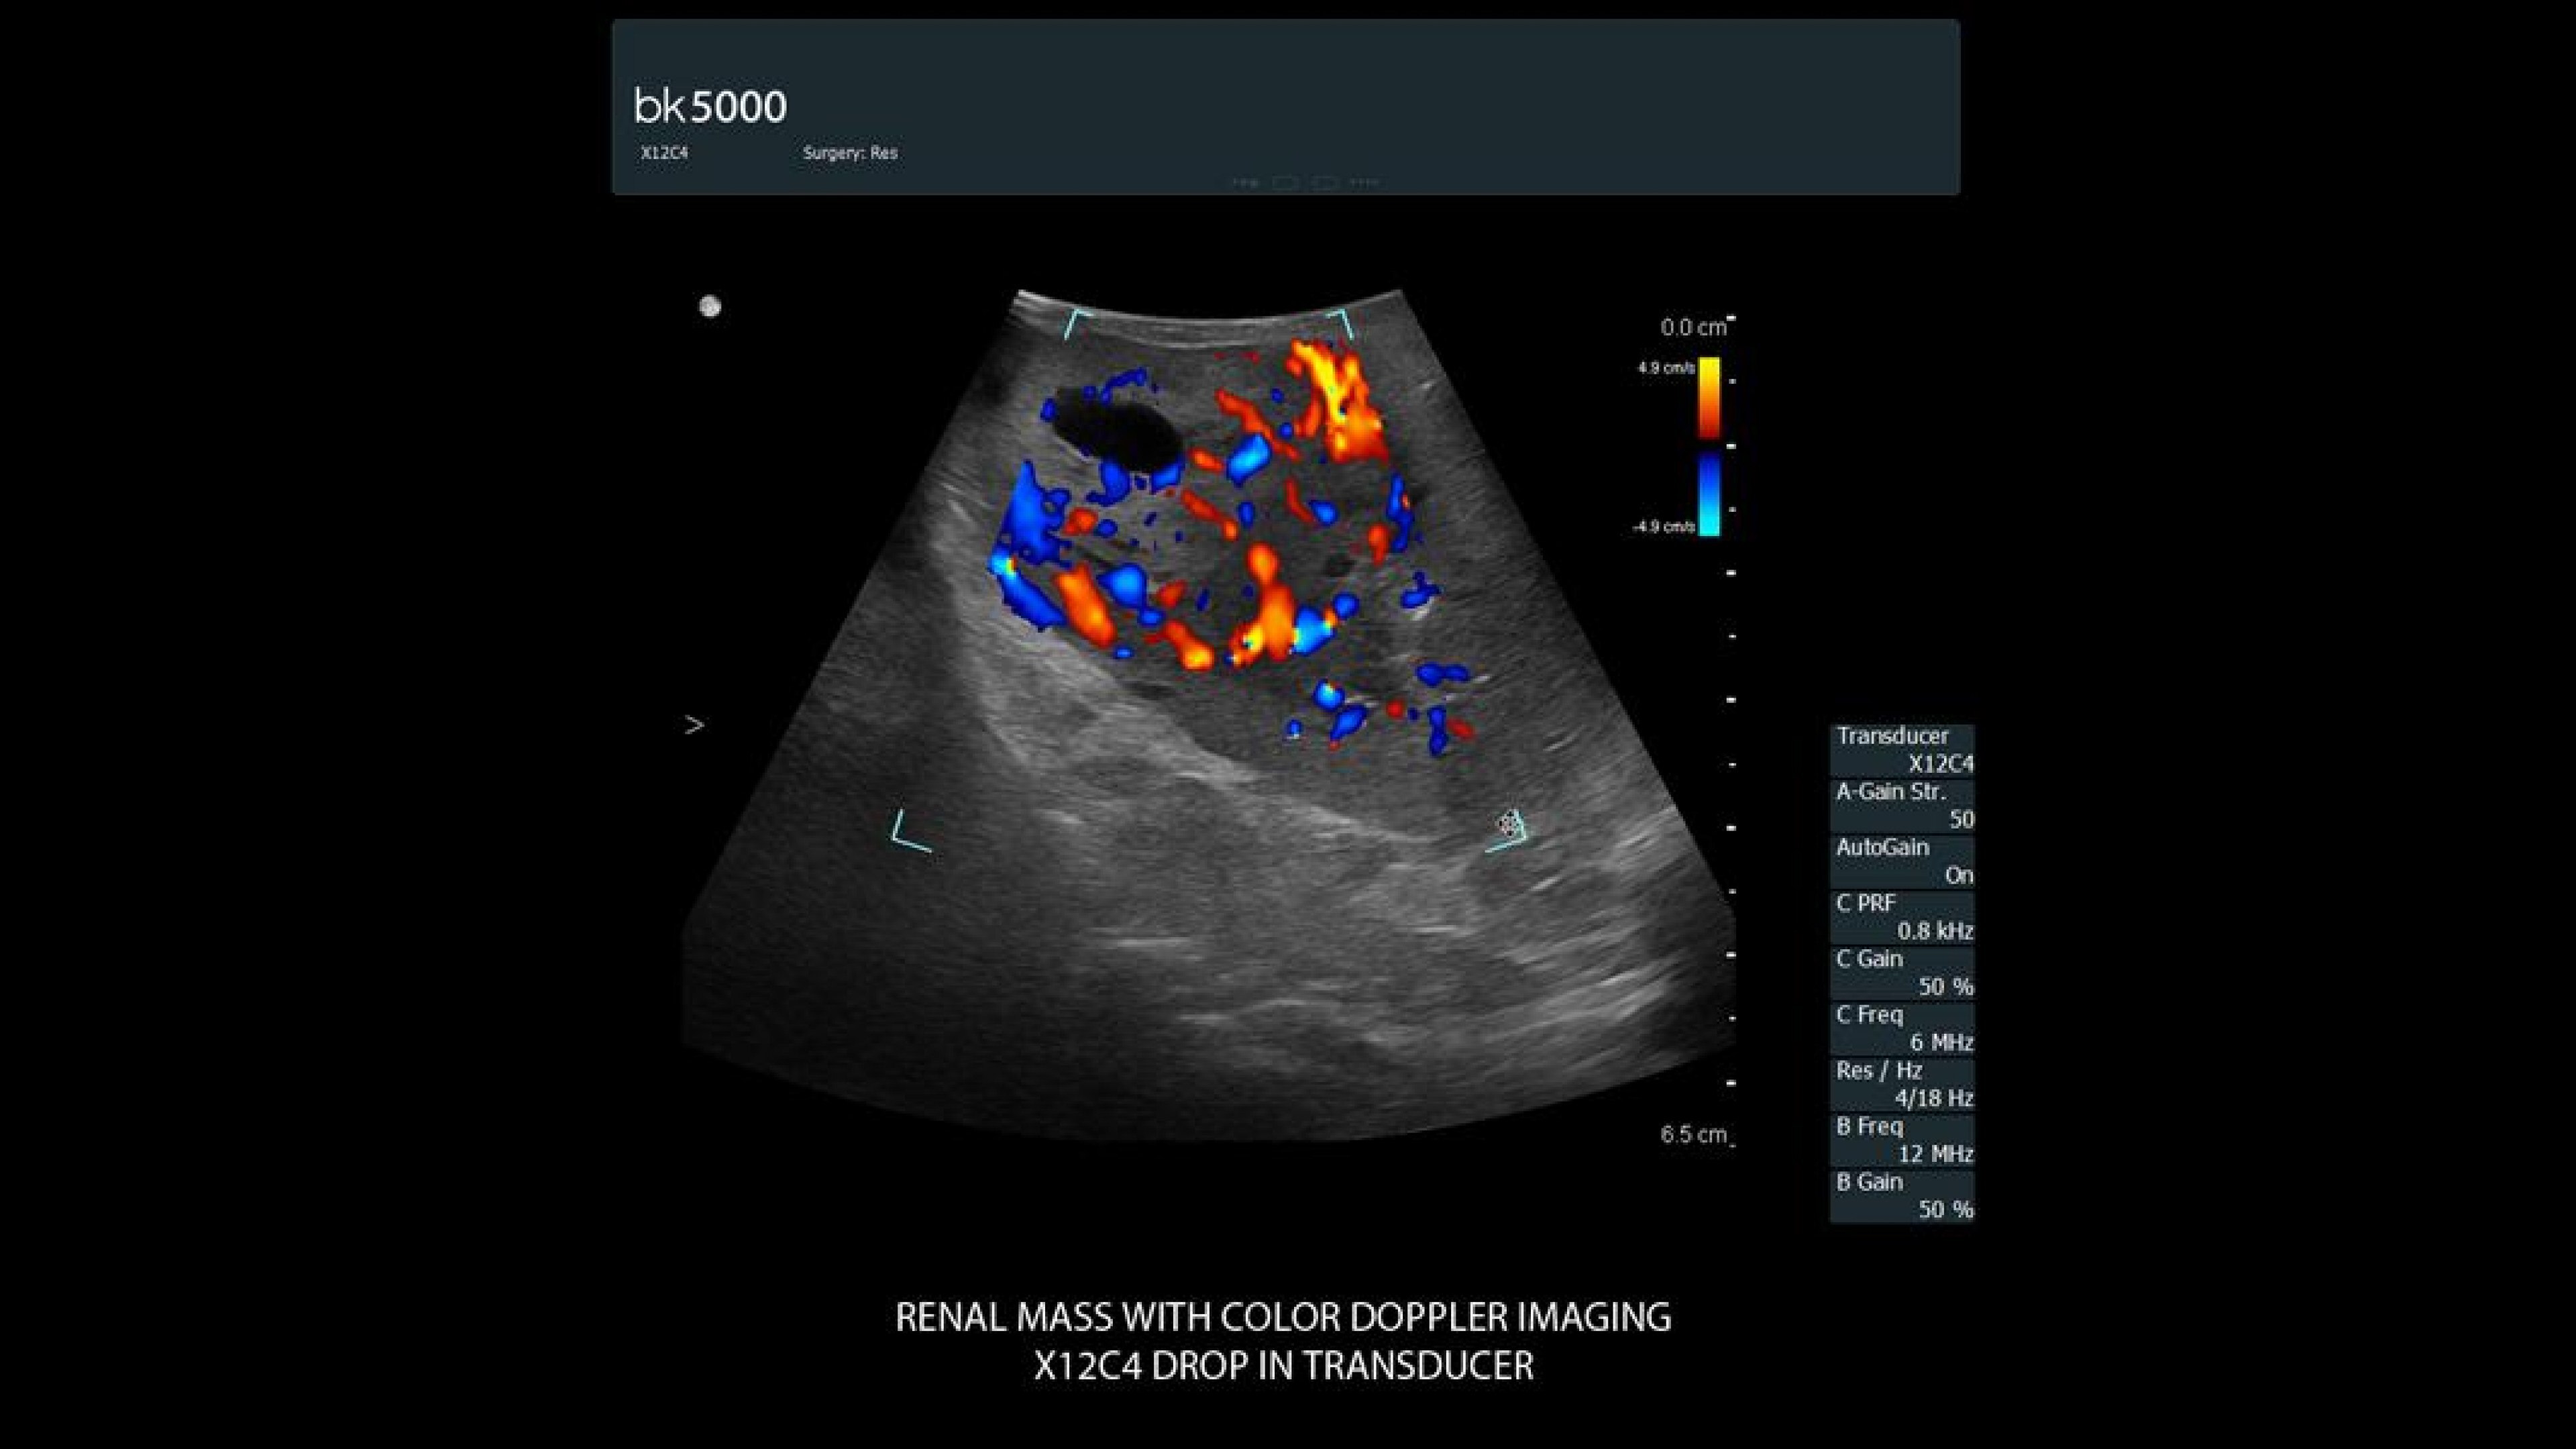

The bk5000 ultrasound system helps surgeons locate and visualize tumor margins, key arteries, and other structures quickly and with greater precision during robotic-assisted surgeries. Its advanced technology delivers exceptional images with high contrast and spatial resolution, providing critical information for surgical decisions.

• Color Doppler and 3D visualization: Sensitive color Doppler identifies blood supply; 3D imaging aids in identifying key anatomical landmarks.